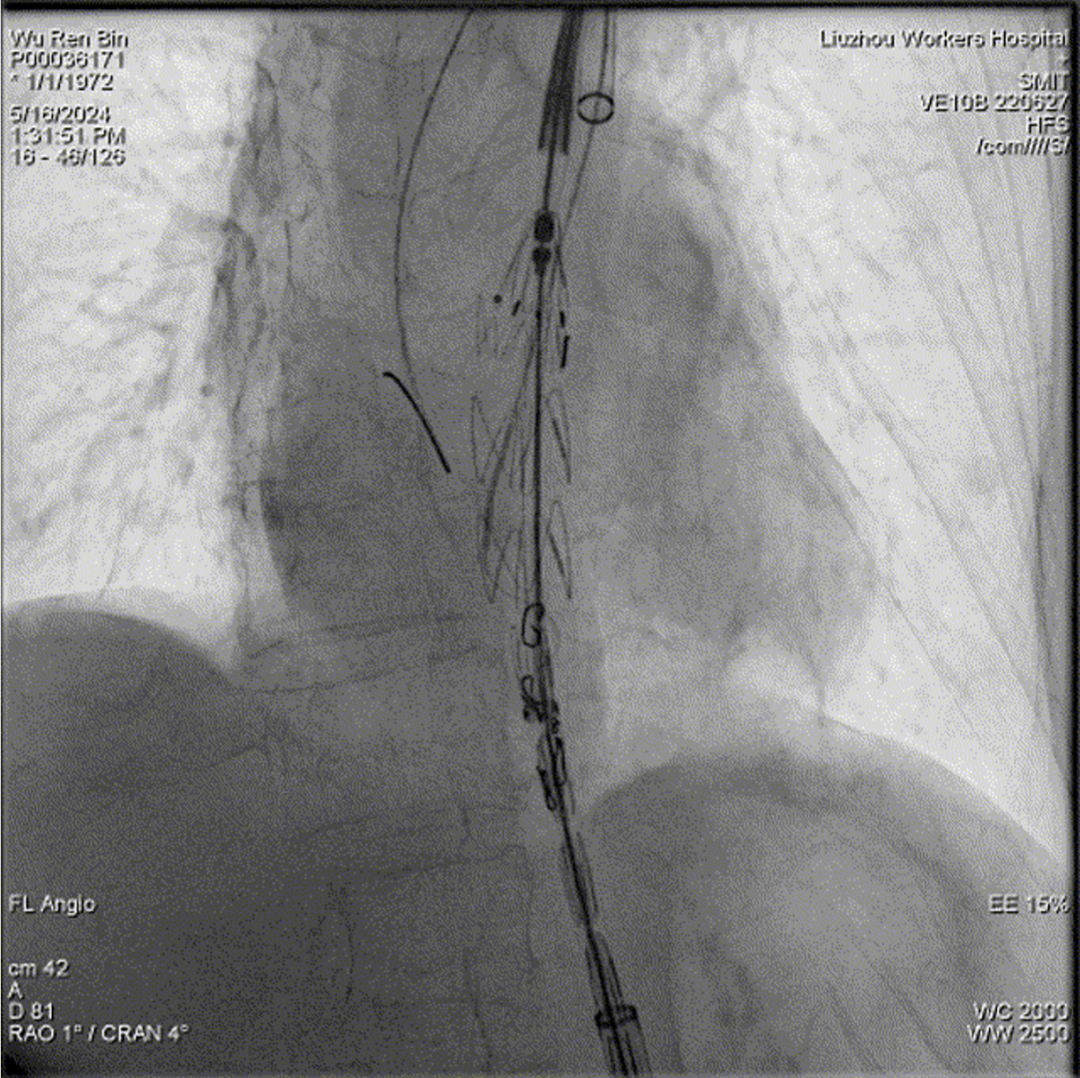

病例2:f-TEVAR(双3D技术,体外三开窗重建弓部三分支)

主动脉弓部壁内血肿累及三分支,胸降主动脉夹层

术中3D影像引导,主体支架精准定位

3D影像引导下,

主体支架窗口与弓上三分支开口对位

依次超选无名、左颈总及左锁骨下动脉

术后造影,支架形态良好,分支血流通畅